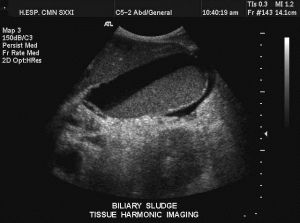

實驗室及輔助檢查:重點排除肝細胞性黃疸和溶血性黃疸。主要結合膽紅素升高;血清鹼性磷酸酶升高是膽汁淤積最具特徵的肝功能異常,通常首先出現;血清γ-谷氨醯轉肽酶在大多數膽汁淤積疾病均不同程度升高;慢性膽汁淤積患者血脂常顯著升高,主要是磷脂和總膽固醇。血清脂蛋白也增加,為低密度脂蛋白增加,高密度脂蛋白降低。有一種異常的脂蛋白X(屬於低密度脂蛋白)增高,具有鑑別意義。影像學檢查了解有否膽道梗阻及梗阻的具體病因。

判定是肝內還是肝外膽汁淤積,需根據超聲、CT、MRCP/ERCP/PTC/超聲內鏡等檢查。